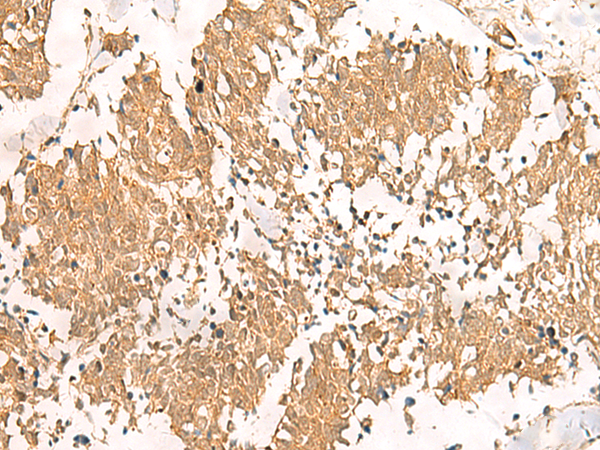

IHC positive control: |

Human tonsil and Human lung cancer |

IHC Recommend dilution: |

30-150 |